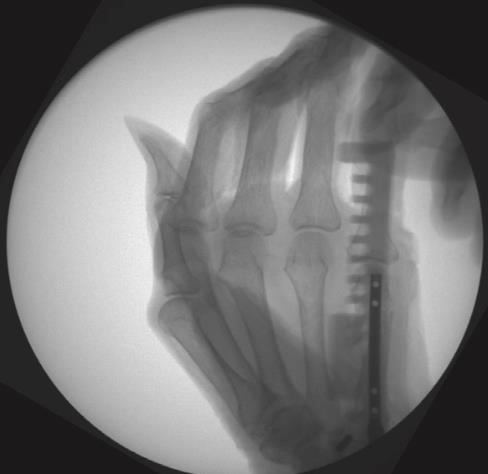

• insert a 1.6mm k-wire into the metacarpal head and advance it to the fracture site

• reduce the fracture under fluoroscopy and advance the k-wire into the metacarpal base

• determine nail length with a measurement ruler or depth gauge and subtract 10mm from the length reading

• for the antegrade approach, flex the wrist while advancing the k-wire through the base of the metacarpal until visible

• insert the cannulated awl over the k-wire, past the soft tissues to the bone surface, with an oscillatory hand motion

• insert the cannulated awl no further than its stop, 10mm or less from subchondral bone